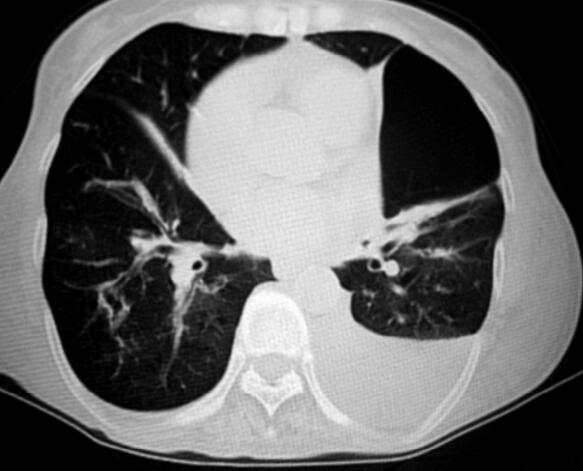

经过上述治疗2天后,患者呼吸困难明显缓解,体温降低,最高37.6℃;咳嗽、咳痰减轻,痰呈黄白色黏痰,量不多,能自行咳出。查体双肺呼吸音粗,可闻及少量湿啰音,散在干鸣音,球结膜无水肿。复查血气分析(吸氧3L/min):pH 7.36,PaO2 53mmHg,PaCO2 65mmHg,HCO-3 35.1mmol/L。复查胸部CT:肺大泡较前增大(图2)。

图2

【临床分析】

患者病情明显好转,也并未出现气胸等气压伤,但患者之前呼吸机参数的调节可能不太合适,吸气压力设置可能过高。关于通气参数的设定,指南推荐采用“患者可以耐受的最高吸气压法”。也就是说,NPPV的吸气压力从低压开始,在20~30分钟内逐渐增加压力,根据患者的感觉能够耐受的最高压力。AECOPD患者NPPV治疗平均的吸气压力为17~18cmH2O。

该患者上机前有肺气肿和多发肺大泡的病史,具有气压伤的高危因素,呼吸机参数的调节时应该予以认真考虑,仔细权衡利弊,不能完全根据指南推荐意见来调节,应该以最小的吸气压力来满足临床治疗的需要。